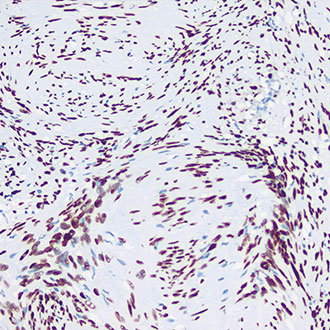

p53

p53 -